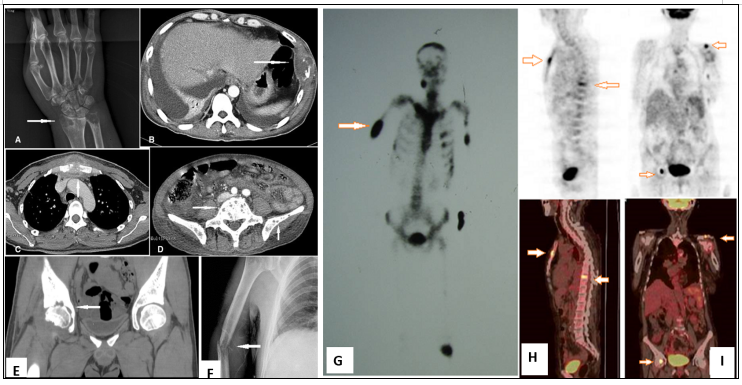

马尔尼菲篮状菌可以引起溶骨性病变。感染性疾病引起溶骨性破坏及坏死并不多见,包括马尔尼菲篮状菌、诺卡菌、放线菌、分枝杆菌等的感染,尤其是NTM。我们曾有一例年轻女性患者,初始诊断马尔尼菲篮状菌,经过治疗,肺部及原有的皮肤病灶显著改善,但患者突发腰痛,就诊时已无法走路(图18)。后经腰椎穿刺活检及组织培养和病理证实既有马尔尼菲篮状菌,又有堪萨斯分枝杆菌。抗感染治疗效果不理想,患者出现截瘫,后续积极抗感染及手术治疗。我们既往可能不太关注感染性疾病累及的骨性病变,而马尔尼菲篮状菌,尤其是HIV阴性马尔尼菲篮状菌,值得我们更多关注。

图片

图18  HIV阴性TSM患者溶骨破坏影像学表现